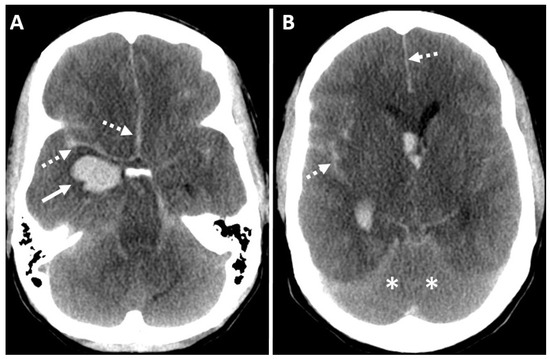

7.5. Computed Tomography Angiography (CTA) Brain

7.6. Computed Tomography Perfusion (CTP) Brain